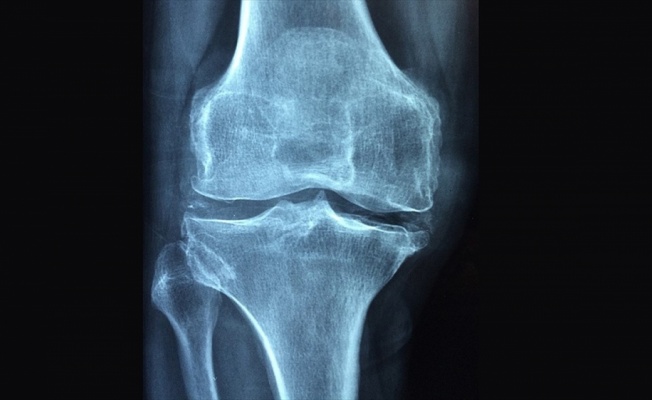

Uzmanlar, osteoporozun tüm dünyada 3 kadından, 50 yaş üzerindeki 5 erkekten birini etkileyen bir sorun olduğunu, hastalığın kırık olmadığı sürece ağrı yapmadığı için sessiz ve sinsi ilerlediğini belirtti.

"Osteoporoz, tüm dünyada 3 kadından birini ve 50 yaş üzerindeki 5 erkekten birini etkileyen global bir sorunudur." diyen Kutsal, "Osteoporoz, tüm dünyada 200 milyon kadını etkiliyor. 60-70 yaşlarındaki kadınların üçte biri, 80 yaşlarındaki kadınların üçte ikisi bu hastalıktan etkileniyor. 50 yaşın üzerindeki kadınların yaklaşık yüzde 30'unda en az bir kırık bulunuyor. Dünyada her yıl 1,5 milyon kalça kırığı oluşuyor. Yaşlanan popülasyon nedeniyle artması bekleniyor." bilgisini verdi.

Prof. Dr. Kutsal, 2050 yılına kadar her sene global olarak 21,3 milyon kalça kırığı olacağının öngörüldüğünü ifade ederek bu nedenle osteoporoz açısından risk altında olan kişilerin mutlaka hekim tarafından değerlendirilmeleri ve korunmaya yönelik önlemlerin alınması gerektiğini vurguladı.

HÜ Tıp Fakültesi Fiziksel Tıp ve Rehabilitasyon Anabilim Dalı Öğretim Üyesi ve Türkiye Osteoporoz Derneği Genel Sekreteri Prof. Dr. Oya Özdemir de "Osteoporoz en sık görülen metabolik kemik hastalığı ve ilerleyen yaşla birlikte sıklığı artıyor. Osteoporoz, kırık olmadığı sürece ağrı yapmadığı için sessiz ve sinsi ilerleyen bir hastalık." diye konuştu.

Osteoporoza bağlı kırık gelişmesinin kişinin sağlığını olumsuz etkilediğini dile getiren Özdemir, omurga kırıklarının sırt ve bel ağrısına neden olarak hastaların yaşam kalitesini azalttığını söyledi. Özdemir, osteoporoz tanısının erken ve doğru şekilde konmasının oldukça önemli olduğunun altını çizerek menopoz sonrası dönemdeki kadınlar ve 50 yaş üzerindeki erkeklerin osteoporoz risk faktörleri açısından mutlaka incelenmesi gerektiğini vurguladı. Özdemir, "65 yaş üzeri tüm kadınlar ile 70 yaş üzeri tüm erkeklere kemik dansimetresi ile osteoporoz açısından inceleme öneriyoruz." açıklamasında bulundu.